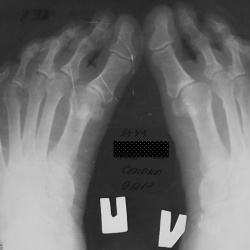

Пациентка 50-го года рождения, с детсва диагностировано продольное плоскостопие 1-2 степени. С декабря 2010 года отмечает появление деформации стоп ( приведение переднего отдела во внутрь),...